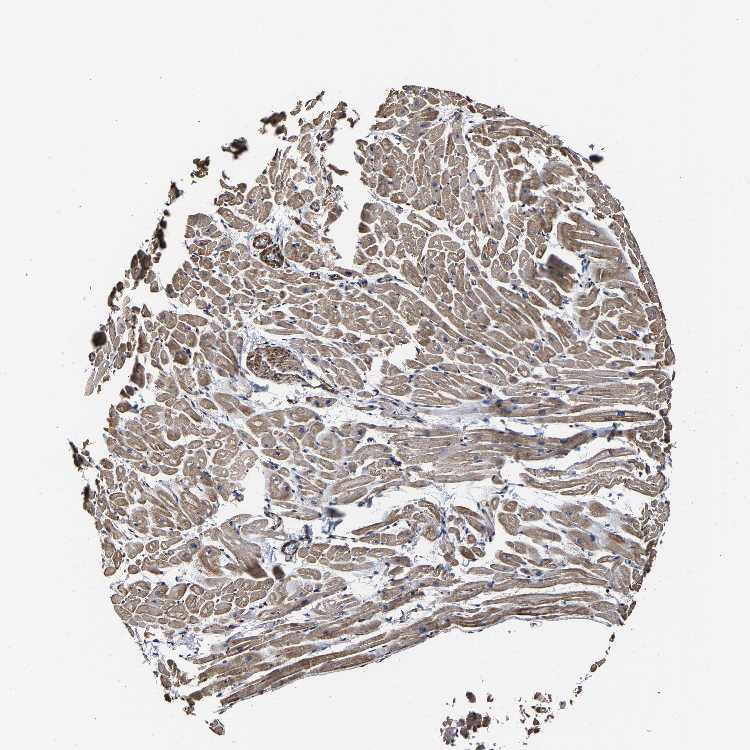

SSH3